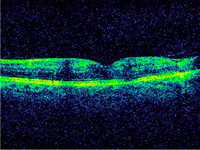

El paciente de la

Figura 1 presenta una hemorragia foveal que afecta a las capas externas, asociada a edema cistoideo. Tras la resolución de la misma (

Figura 1. Hemorragia foveal. Se aprecia como zona hiperreflectiva que en este caso afecta a capas externas, asociada a edema cistoideo y engrosamiento retiniano foveal.

Figura 2. Resolución de la hemorragia foveal de la Figura 1. La reabsorción de la hemorragia y del edema macular dan paso a una normalización del contorno foveal, con atrofia de las capas externas.